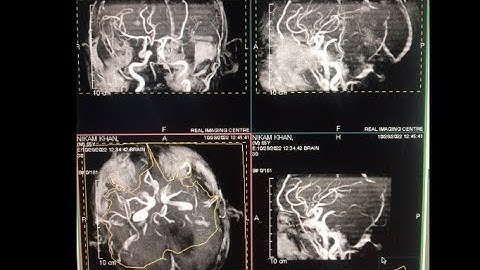

Diffusion weighted images of Brain on 0.3 tesla MRI